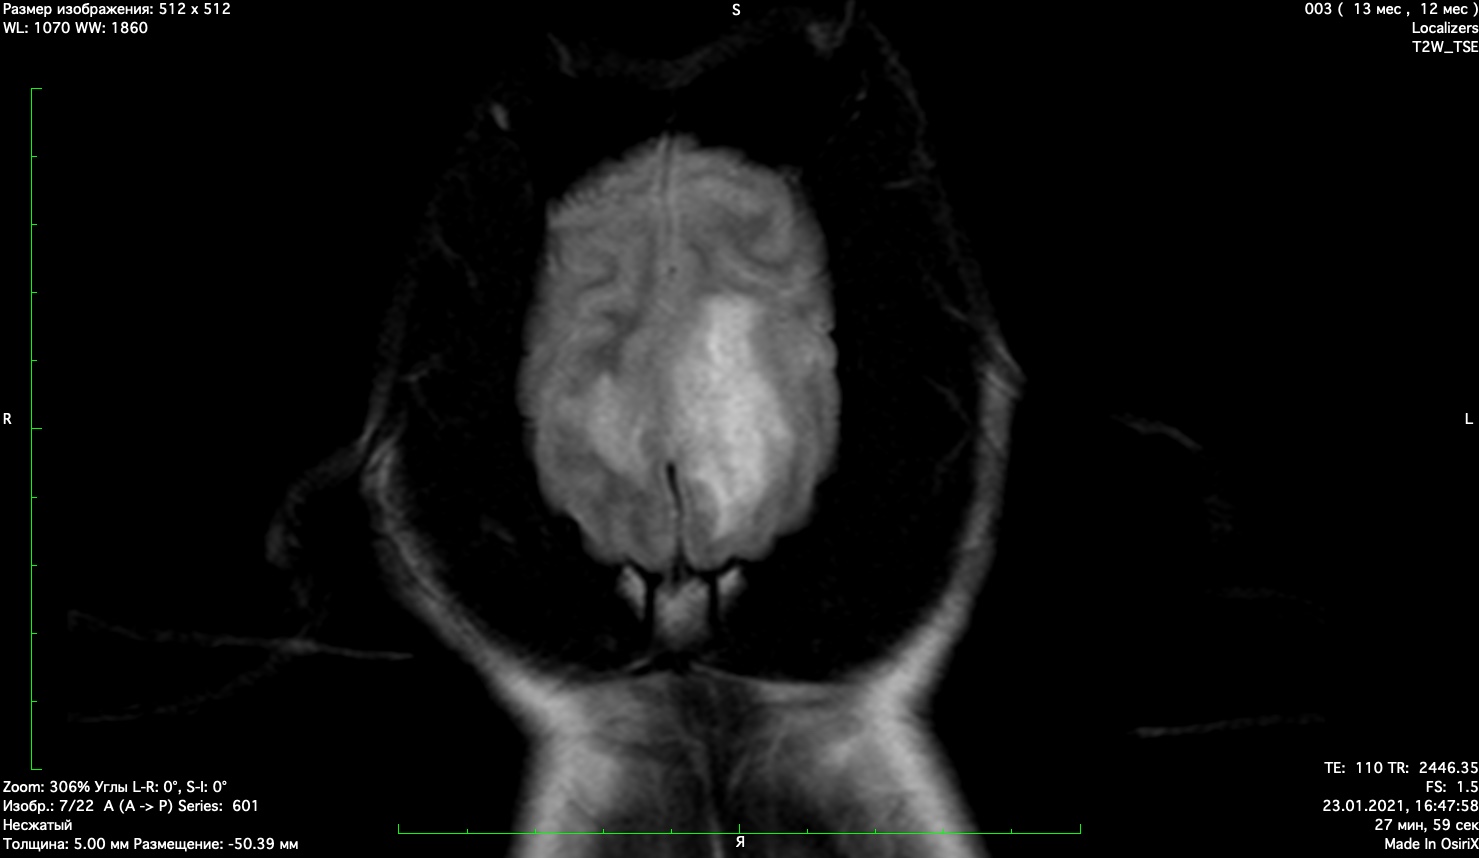

При проведении мрт диагностики установлено признаки мультифокального поражения головного мозга поставлен диагноз гранулематозный менингоэнцефалит неизвестной этиологии. Начато иммуносупрессивное лечение